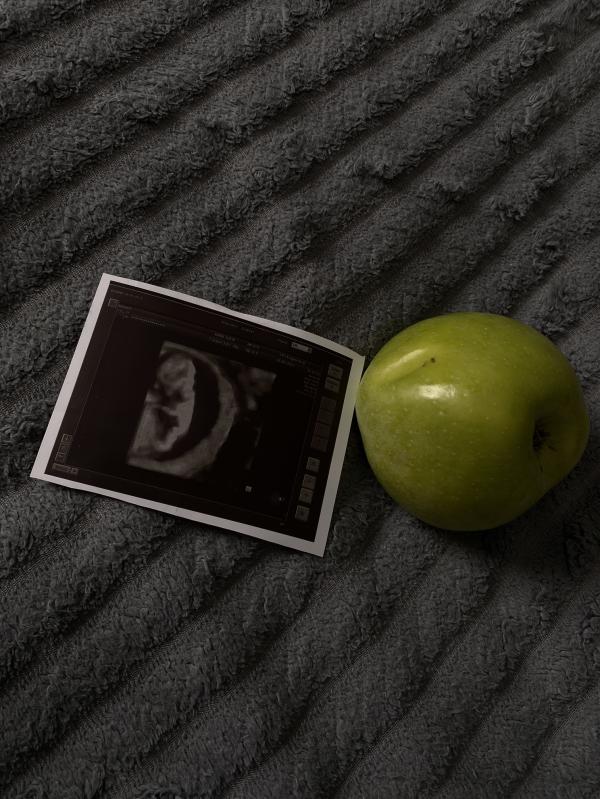

Такая идея классная с фруктами размера малыша делать фото🔥